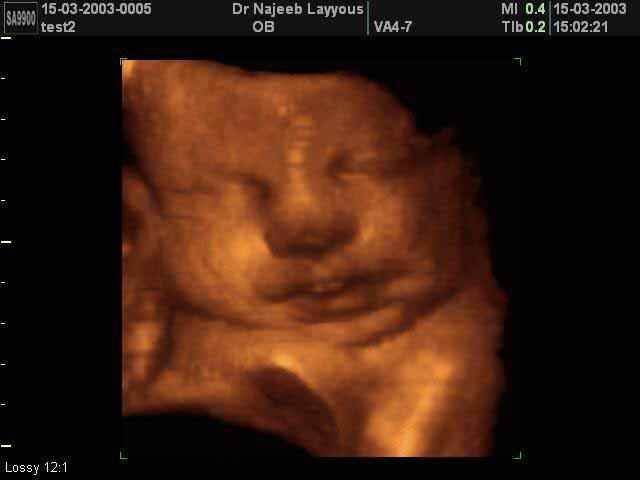

- Fetal Face Ultrasound Photos

- 3D Fetal Profile Ultrasound Scan Photos

- The Clinical Advantages of 3D and 4D Ultrasound

- Definition and Features of Four Dimensional Ultrasound

- Uses of 4D Ultrasound scan

- The importance of 4D ultrasound imaging in pregnancy